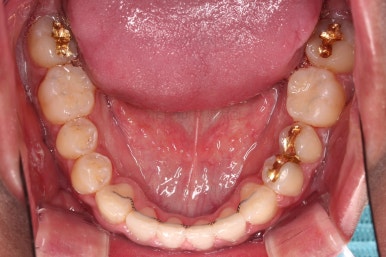

부산교정 장치를 부착했습니다.

이번에 선택하신 장치는 자가결찰 세라믹 장치에요. 스스로 철사를 묶는(결찰) 뚜껑이 달린(자가) 세라믹 성분의 장치인데요.

기능적으로도 우수하고, 세라믹이다 보니 미적으로도 장점이 있습니다.

이번 환자분은 엠파워 클리어라고 하는 장치를 사용했으며 흔히 아신느 클리피씨와 동일한 계열의 장치입니다.

장치 부착 직후의 느낌 참고해 주시고요.